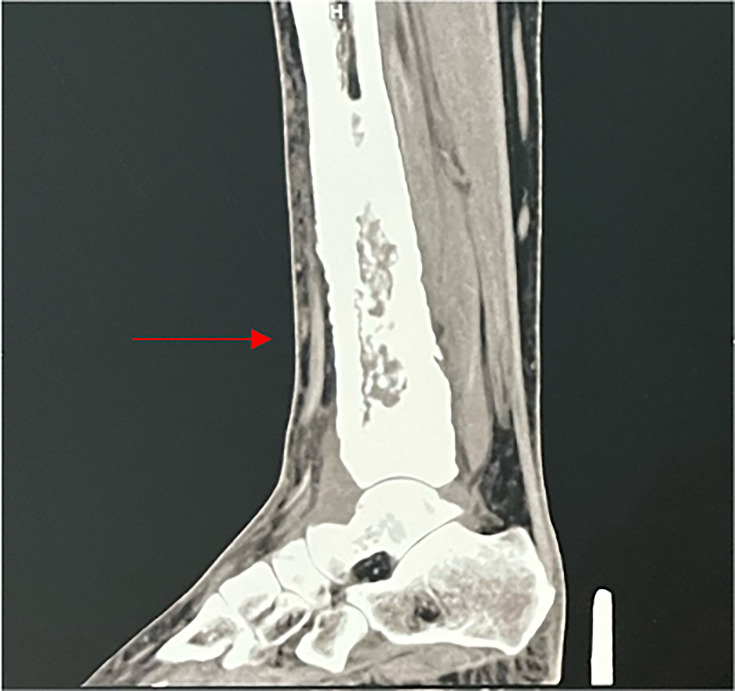

Tuberculosis is a major scourge, posing a serious public health problem in countries where it is endemic. Osteoarticular involvement accounts for 3-5% of all tuberculosis cases and 10-15% of extrapulmonary tuberculosis cases. We report a case of tibial osteitis caused by Mycobacterium tuberculosis in a 52-year-old female patient who presented to the trauma department at the Mohammed V Military Teaching Hospital with a painful swelling of the lower part of her left leg. Standard X-rays and computed tomography scans revealed bone involvement, specifically in the tibia. Additional investigations revealed pulmonary consolidation and splenic nodules. Microscopy (Ziehl-Neelsen staining), GeneXpert MTB/RIF and histopathological examination all returned positive results for M. tuberculosis. In an endemic context, any persistent and atypical bone lesion should raise suspicion of osteoarticular tuberculosis to enable rapid diagnosis and appropriate therapeutic management. In the absence of malignant tumours and other differential diagnoses, the diagnosis of skeletal tuberculosis must be considered, even in the absence of specific clinical signs.